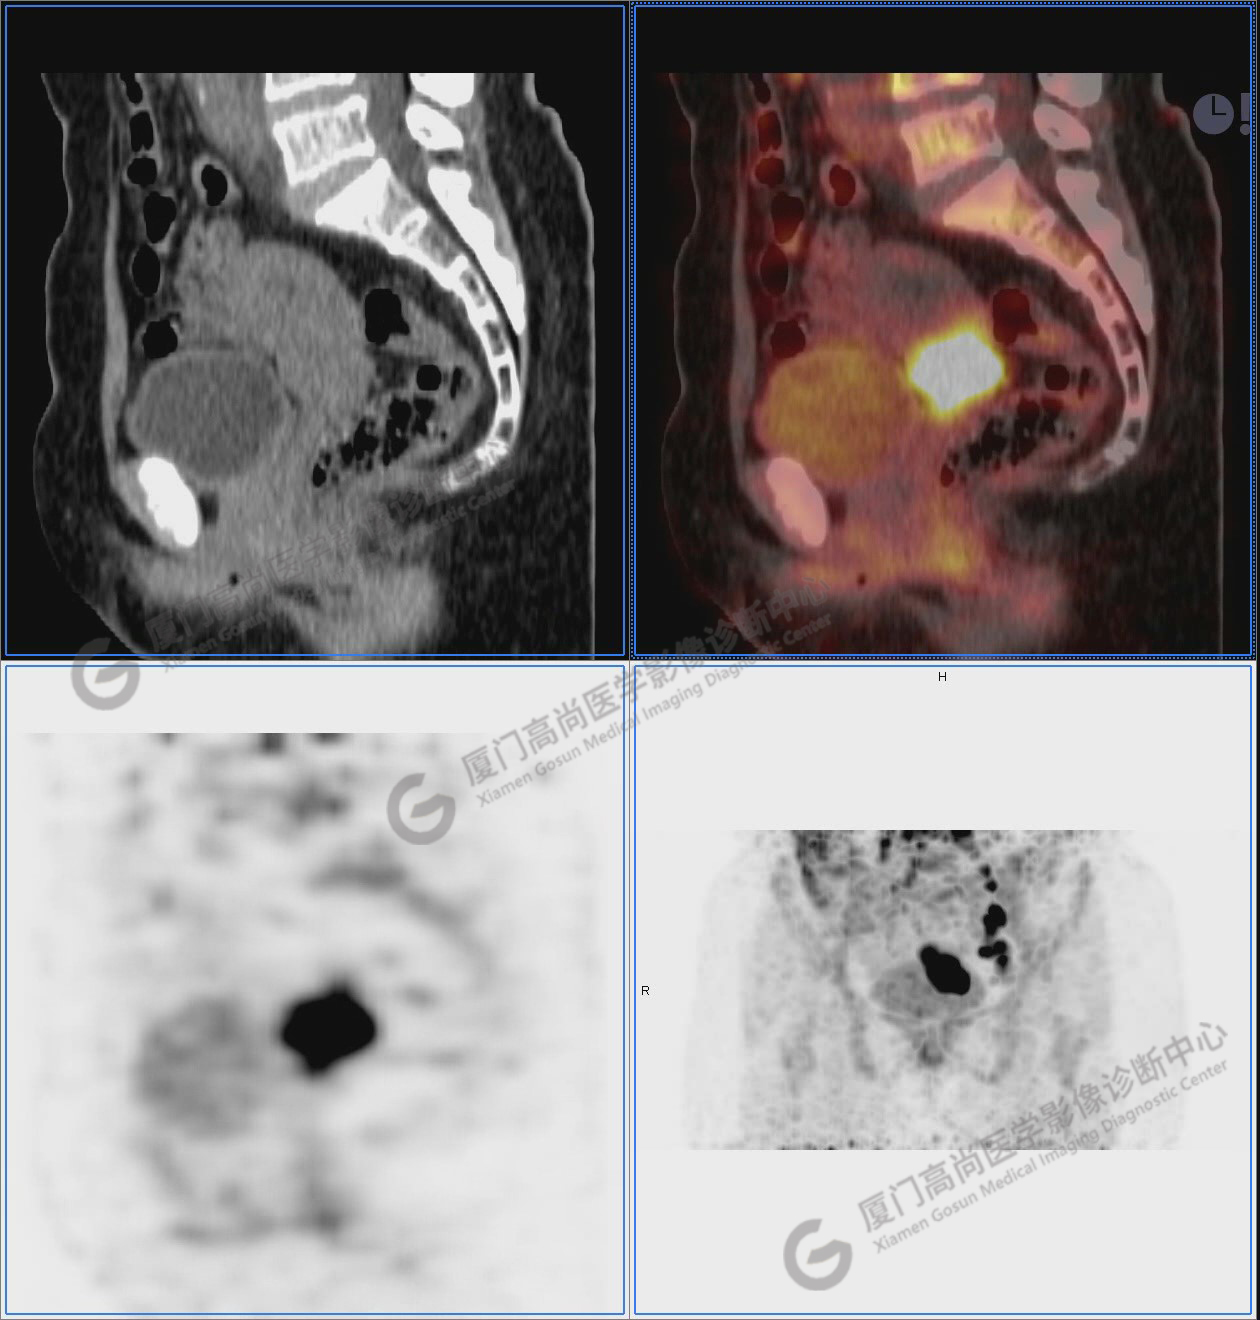

圖10-11:子宮頸軟組織腫塊,代謝異常增高,考慮為宮頸癌。

圖12-13:延遲2小時后,宮頸腫塊糖代謝進一步增高。